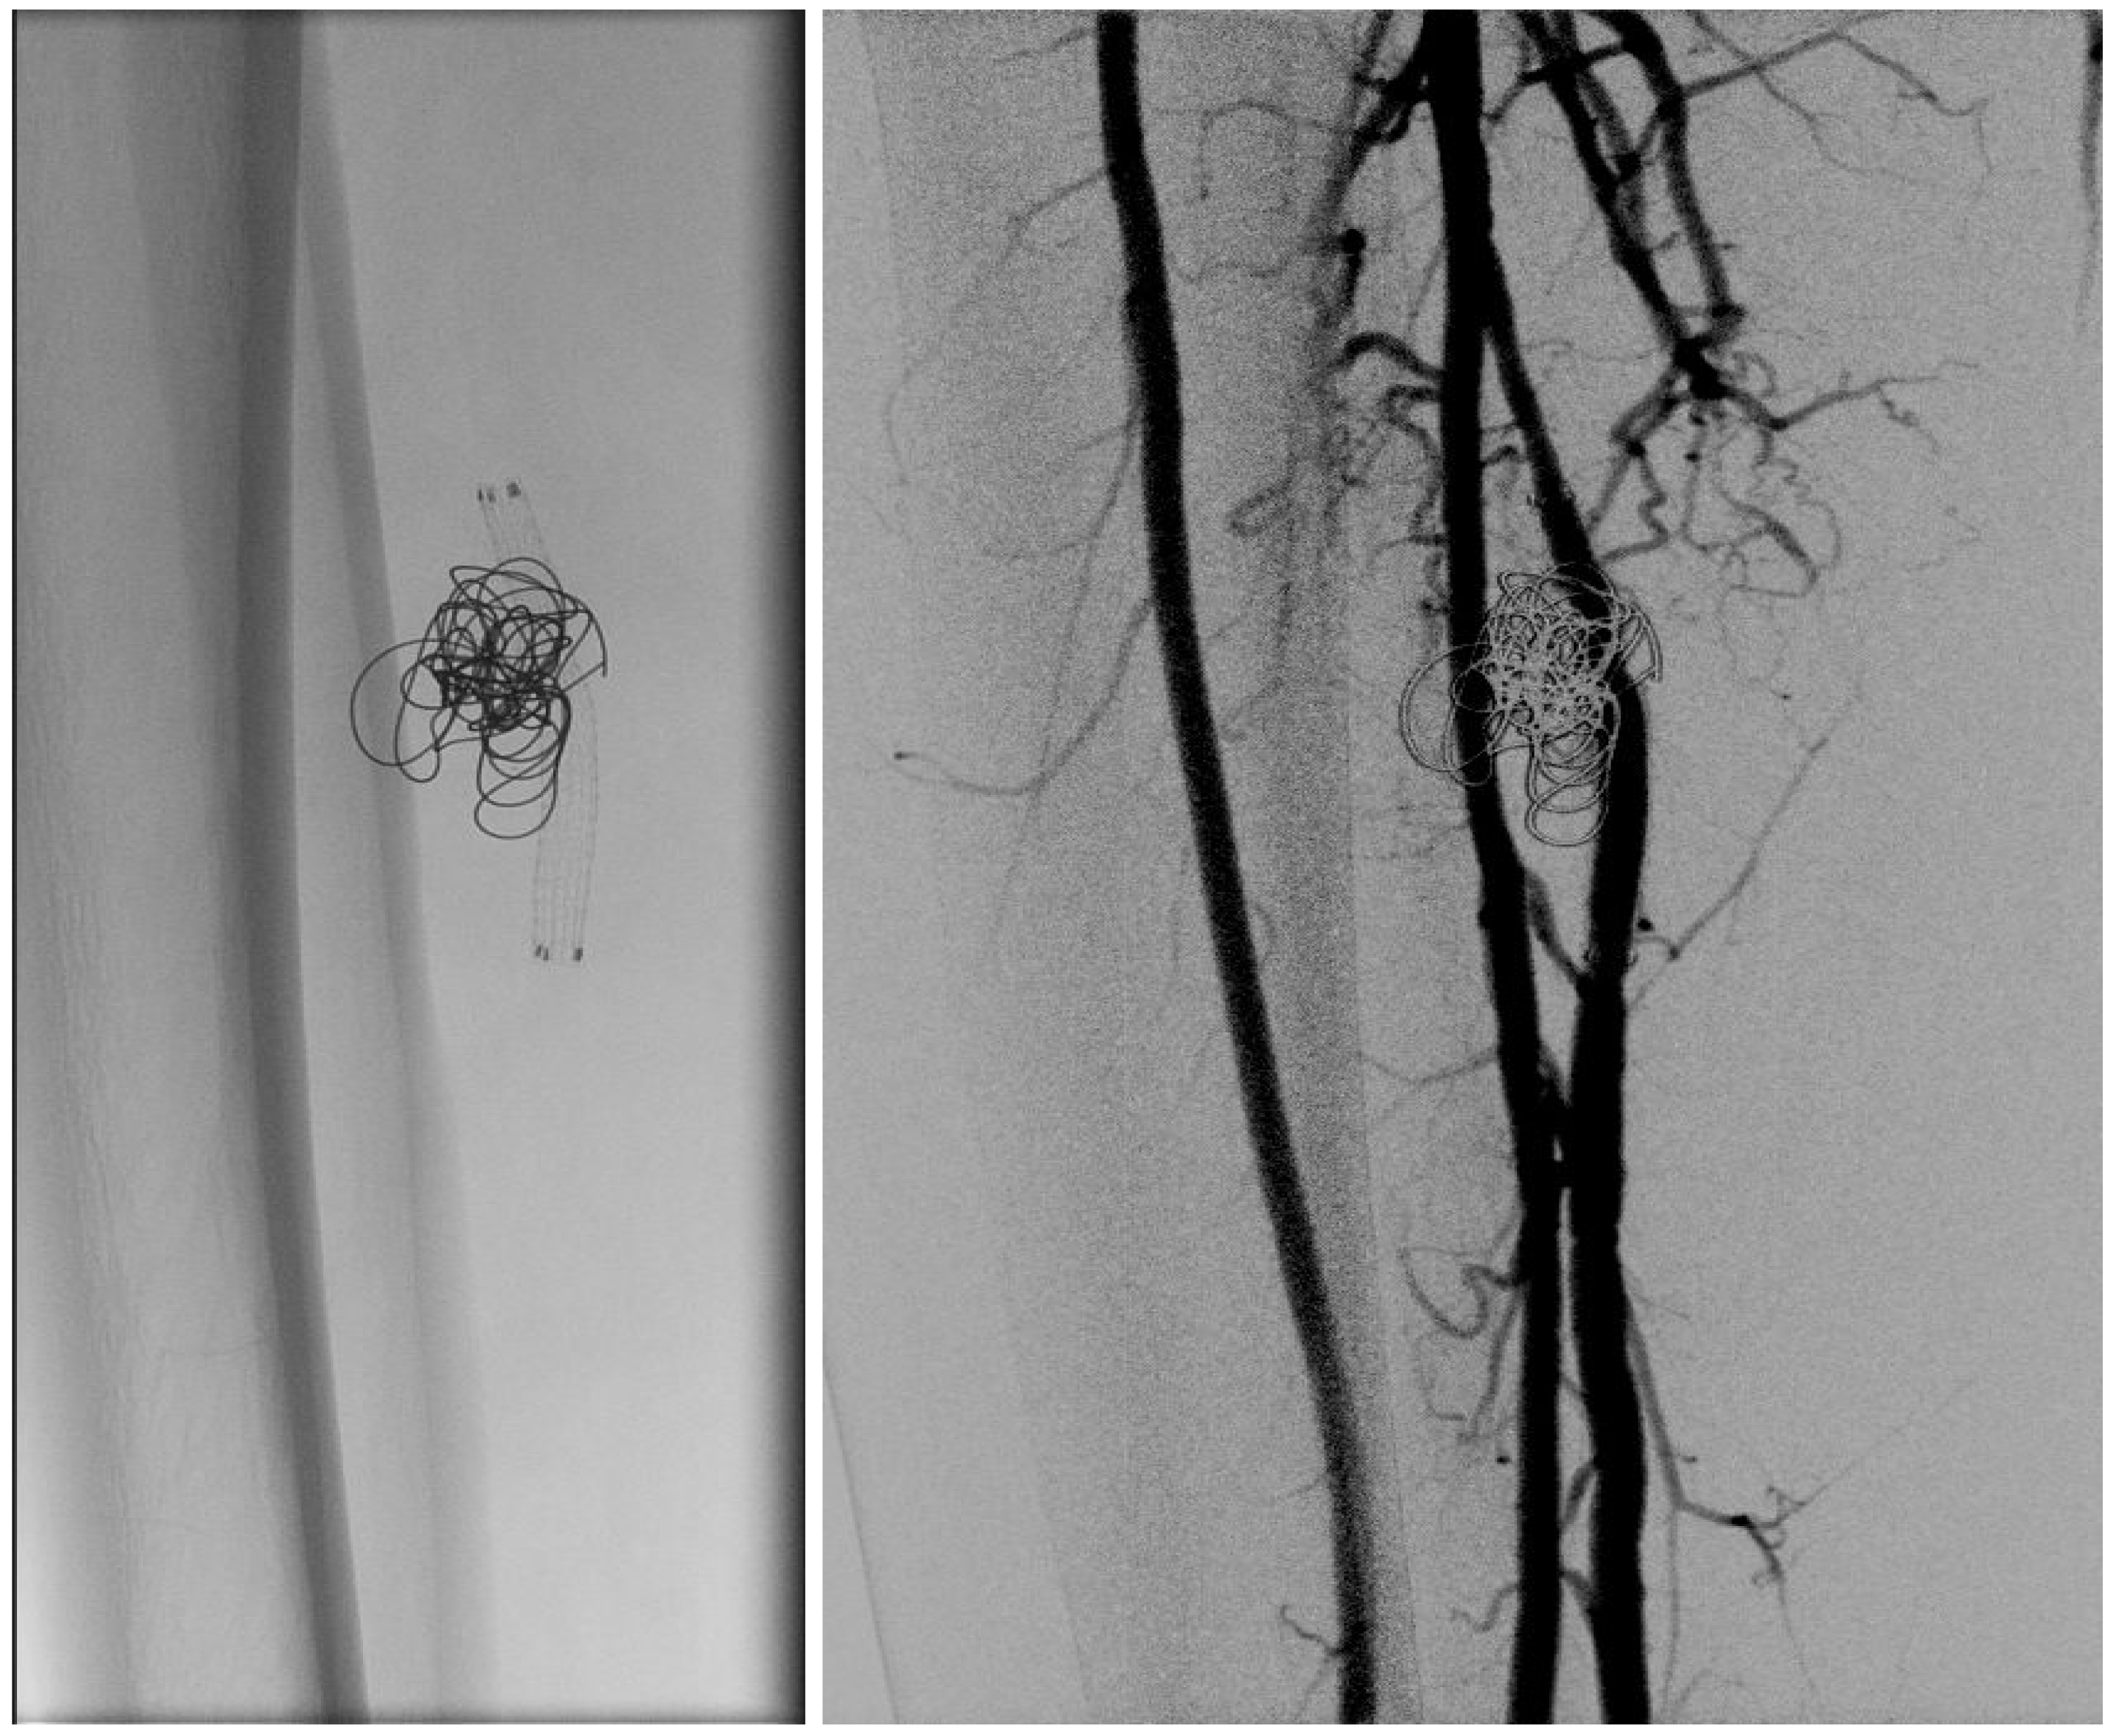

In light of a symptomatic aneurysm, treatment was offered to the patient. After discussing the risks of open and endovascular treatment options with the patient, an endovascular approach was opted for. The presence of a large aneurysm with an AV fistula and venous congestion posed an increased risk of significant bleeding complications associated with open surgery. An antegrade femoral access was obtained via a 5F sheath (Terumo, Shibuya-ku, Tokyo, Japan). After obtaining an angiogram, two coils were deployed in the aneurysm sac (Concerto PGLA helical PV-20-50-Helix and Concerto PGLA 3D PV-18-40-3D, Medtronic, Minneapolis, MN, USA), with the aim of causing sac thrombosis and obliterating the flows from multiple AV fistulas. As anticipated, this did not lead to complete occlusion of the aneurysm and AV fistula. A retrograde pedal access was obtained, and cannulation of the PTA was successfully performed with a V14 guidewire (Boston Scientific, Marlborough, MA, USA) (Figure 2 and Figure 3). After obtaining guidewire access, the aneurysm was excluded with a stent graft (Viabahn Endoprosthesis 5 mm × 50 mm, WL Gore, Flagstaff, AZ, USA). Immediately after the procedure, angiography control visualized complete exclusion of the pseudoaneurysm, occlusion of the sac, and absence of any AVF (Figure 4). Postoperatively, the patient reported pain reduction. Both pedal pulses were palpable. Postoperative antithrombotic therapy included aspirin 100 mg and clopidogrel 75 mg daily for 6 months. Additionally, Class 2 compression stockings were recommended for 1 month. After 18 months of follow-up, the patient was free of symptoms, and the stent graft was patent.

Figure 4.

(Left) to (right). Coils and Viabahn stent graft. Post-stenting angiogram showing excluded aneurysm and fully deployed Viabahn.